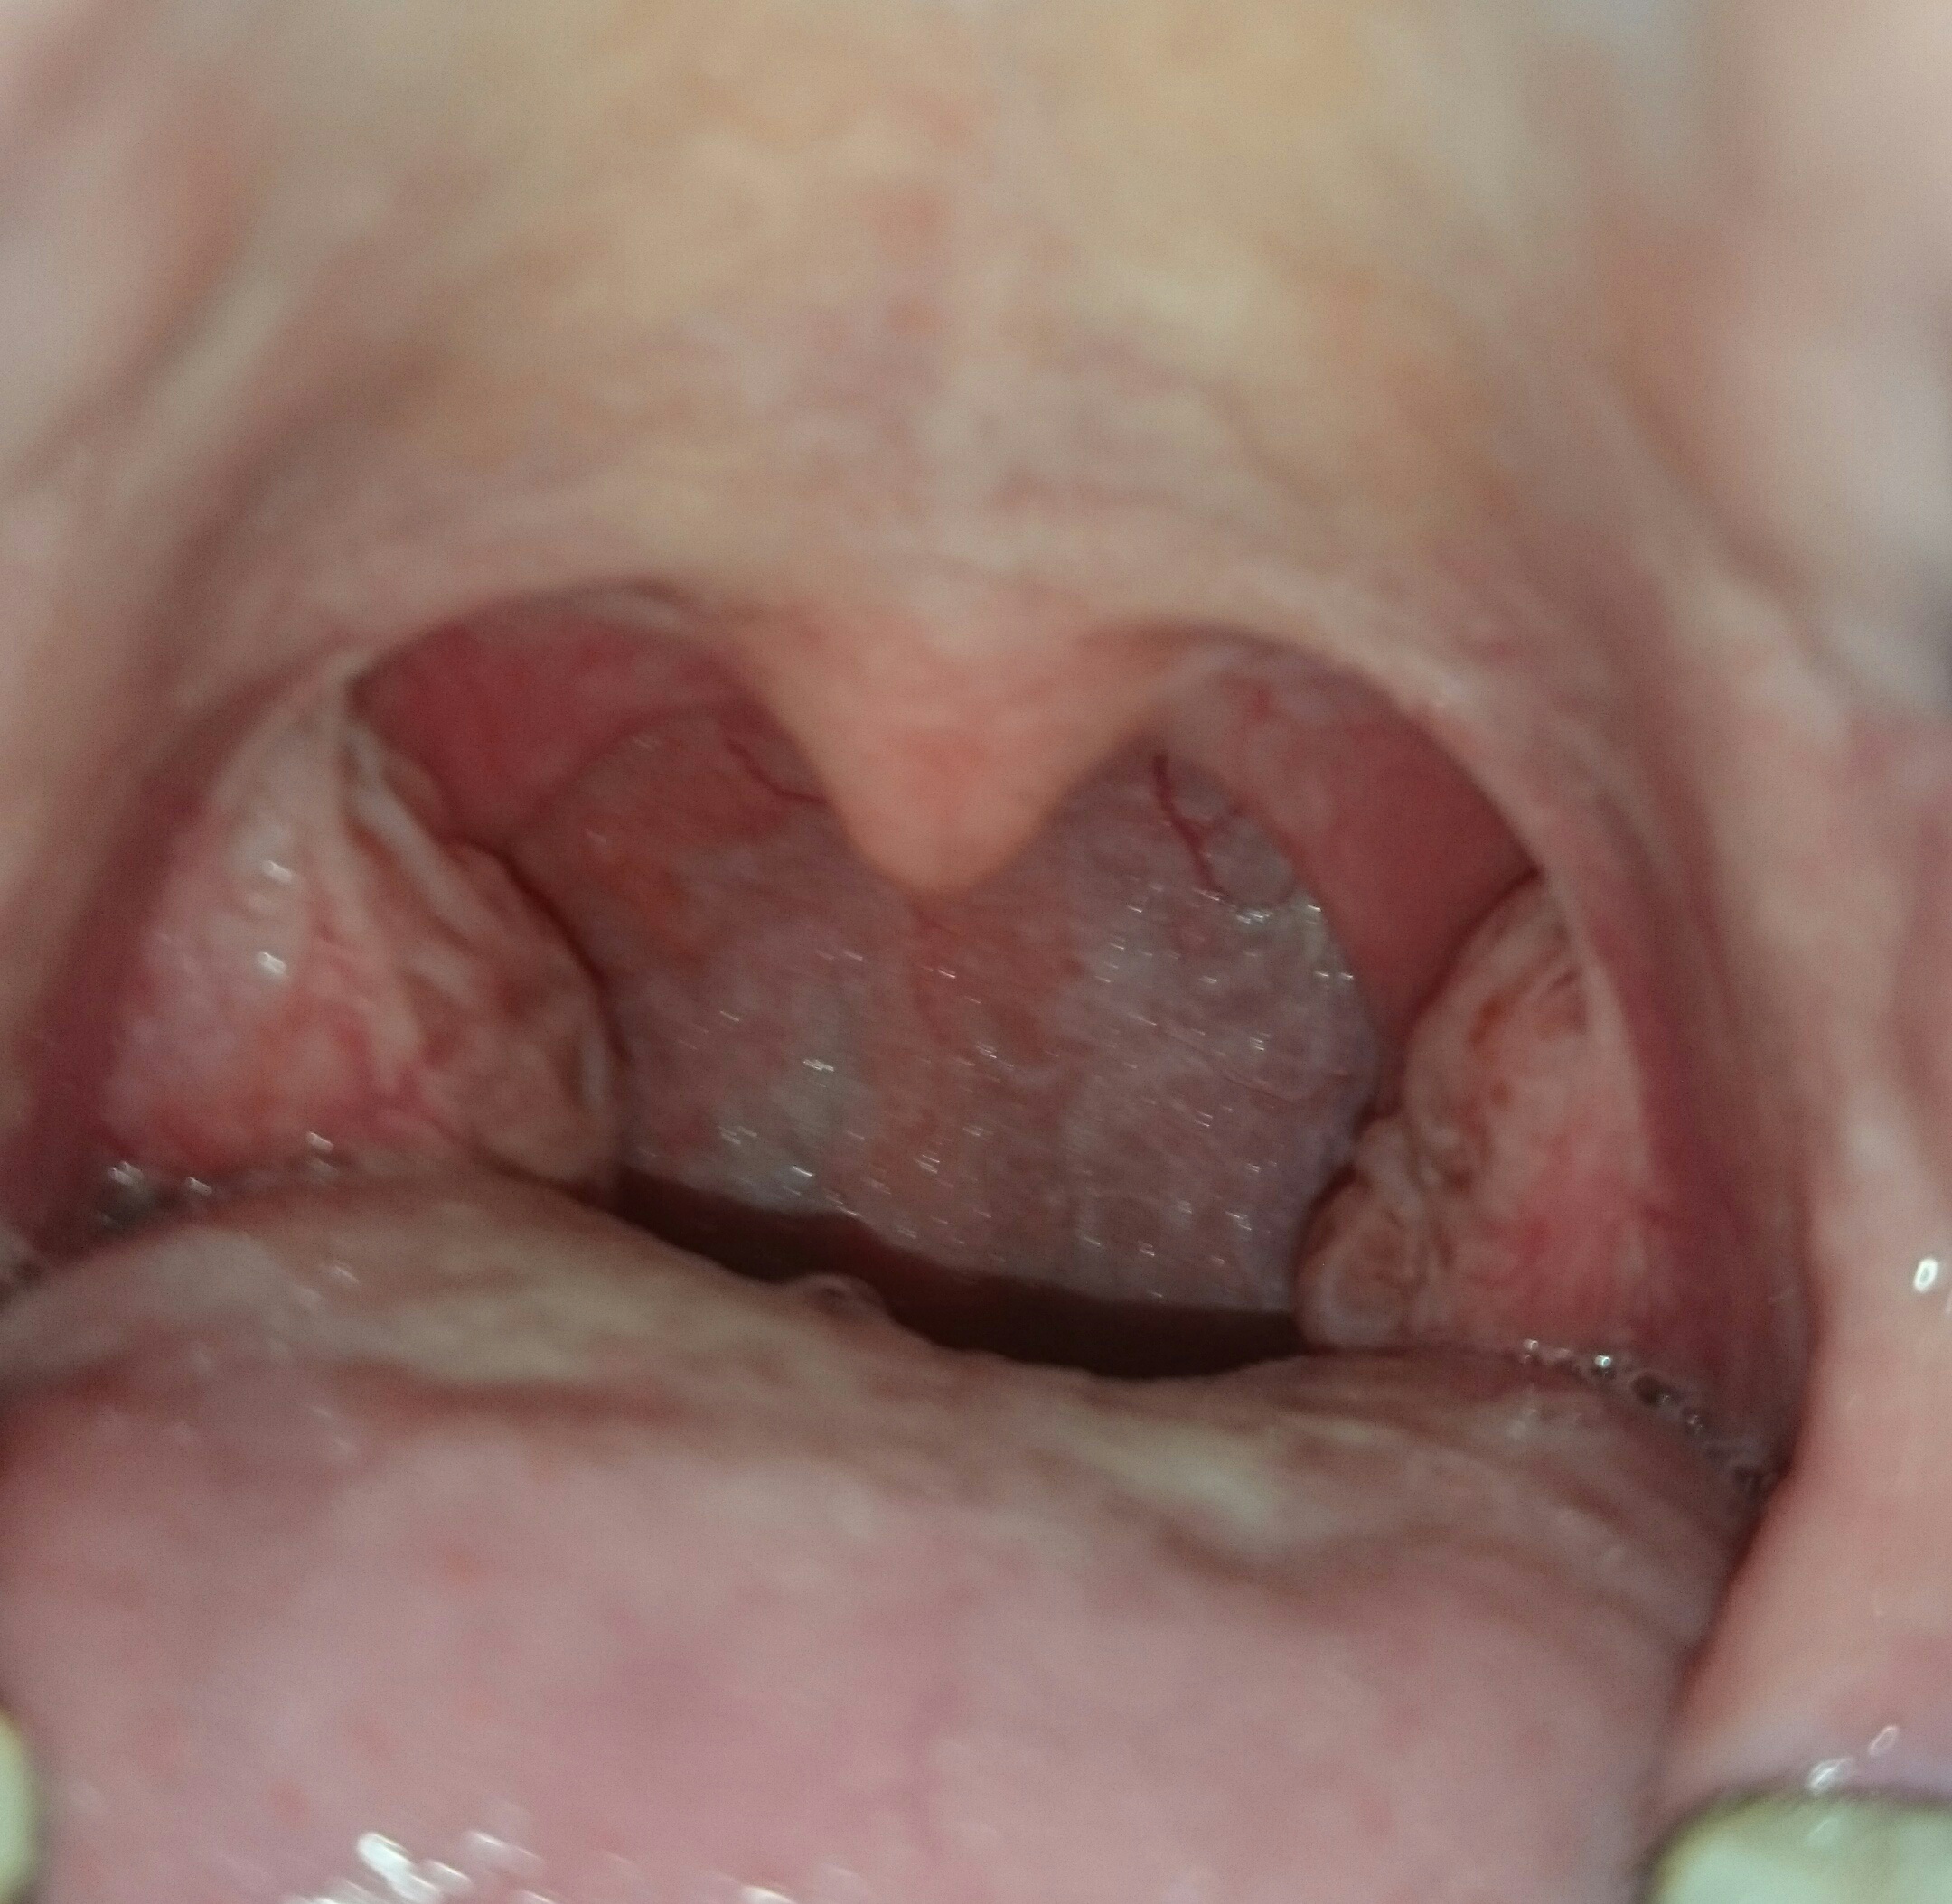

Typischerweise setzen die Beschwerden sehr plötzlich ein. Die Erkrankung klingt mit einer .Die Gaumenmandeln sind mit den anderen Mandeln des Rachenrings ein wichtiger Bestandteil unseres Immunsystems. Wenn man außerhalb einer Mandelentzündung weiße Stippchen auf den Mandeln sieht, dann sind das Tonsillensteine oder Tonsillenpfröpfe, erklärt Thomas Deitmer, Generalsekretär der .atRachenentzündung: Ursachen und Symptome | praktischArztRpraktischarzt. Was sind die Ursachen und Risikofaktoren einer Mandelentzündung? Die Mandelentzündung kommt insbesondere bei Schulkindern vor, . Im Spiegel erkennt man einen geröteten Rachen. Eine akute Entzündung der Mandeln beginnt meist rasch.Rachenmandeln sind Ansammlungen von Lymphgewebe , wo die Nasengänge mit dem Rachen verbunden sind. Typische Symptome sind . Allgemeines Unwohlsein. Stimme wirkt kloßig, meist nicht heiser.Rachenentzündungen werden in der Regel durch ein Virus verursacht, können aber auch durch Bakterien wie Streptokokken verursacht werden. In schlimmen Fällen gehen diese Stippchen ineinander über (konfluierend) und reichen über die Gaumenmandeln hinaus (z. Diese geschwollenen Eiterstippchen rufen ausgeprägte Halsschmerzen und Schluckbeschwerden hervor und gehen oft mit .Schlagwörter:MandelentzündungMSD ManualDie Symptome bei einer akuten Mandelentzündung sind ziemlich eindeutig, so dass der HNO-Arzt bei seiner Untersuchung schnell die richtige Diagnose stellen wird. Schluckbeschwerden. Bei Kleinkindern kann sich die Mandelentzündung zu Beginn aber auch nur in Form .) Manchmal dringen Bakterien (meist Streptokokken und Staphylokokken), die den Hals infizieren, tiefer in das umliegende Gewebe ein. Auf den Mandeln entsteht ein weißlich-gelber Belag. geschwollene Lymphknoten. Stimmveränderung.Die Rachen- und die Zungenmandel sind hingegen nicht mit bloßem Auge zu sehen.Agsin Kjasimov (Arzt) Drucken. Auslöser einer bakteriellen Mandelentzündung sind, wie bereits beschrieben, in den meisten Fällen Streptokokken.

Schlagwörter:MandelentzündungRachenentzündungSchlagwörter:MandelentzündungAngina Tonsillaris Bei einer Mandelentzündung, medizinisch auch Tonsillitis genannt, sind die Gaumenmandeln entzündet. geschwollene und gerötete Gaumenmandeln.

Ursachen: Auslöser einer Mandelentzündung ist ein viraler oder bakterieller Infekt, der durch eine Tröpfcheninfektion übertragen wird. Bei Patienten ohne Mandeln kommt es in diesen Fällen oft zu einer .Eine reine Entzündung der Gaumenmandeln ist meist bakterieller Natur. Geschwollene, gerötete Mandeln deuten auf eine Entzündung hin, Eiterstippchen auf den Mandeln sprechen .

Zu den charakteristischen Symptomen einer akuten Mandelentzündung gehören unter anterem Halsschmerzen, Kopfschmerzen und Fieber über 38°C sowie geschwollene und sehr rote Mandeln mit einer gelblichen Schicht.

Alle NetDoktor. Vor allem bei Kindern kann es auch zu Kopf- und Bauchschmerzen sowie Übelkeit und Erbrechen kommen.Halsschmerzen gehen meist auf eine Rachenentzündung durch Erkältungsviren zurück, die auf die Mandeln übergreifen kann.Eine Rachenentzündung (Pharyngitis) kann akut oder chronisch auftreten. Dabei kommt es zu einer bakteriellen Sekundärinfektion der Gaumenmandeln, die zumeist von Streptokokken verursacht wird. Ihre Funktion ist es, Krankheitserreger zu erkennen, aufzuhalten und abzutöten. Geschwollen, gerötet, wund: Wenn sich der Mund- oder Rachenraum entzündet, ist das für Betroffene sehr unangenehm. Rachenmandeln können sich allerdings auch vergrößern, wenn sie durch Viren oder Bakterien infiziert werden, die eine Rachenentzündung verursachen (Halsschmerzen Halsschmerzen Halsschmerzen sind Schmerzen an der Rückwand des . Die Mandeln bestehen aus 1 bis 2 cm dickem lymphatischem Gewebe. Eine bakterielle Entzündung der Gaumenmandeln kommt seltener vor. Entzündungen im Rachen- und Kehlkopfbereich sind relativ häufig.Symptome einer Mandelentzündung. deutlich verstärkter Speichelfluss.Mandelsteine können leicht mit Eiter verwechselt werden. starker Speichelfluss.Die Mandeln erfüllen eine wichtige Aufgabe im Abwehrsystem des menschlichen Körpers.de-Inhalte werden von medizinischen Fachjournalisten überprüft. Meist klingt sie nach ein bis zwei Wochen ohne .Halsschmerzen können unterschiedliche Ursachen haben. Mandelsteine (Tonsillensteine) sind weiß-gelbliche Gebilde, die aus verschiedenen Substanzen in den Gaumenmandeln entstehen.Die Mandeln sind gerötet, geschwollen und – im Falle einer bakteriellen Infektion – scheiden die Mandeln eine weiß-gelbliche, zähe Masse, Zellabfälle (Detrius), die so genannten Stippchen, aus. Inhaltsverzeichnis.

Acht von zehn Halsentzündungen werden . Im sogenannten sekundär lymphatischen Gewebe der Gaumenmandeln führt der Kontakt mit Fremdstoffen wie zum Beispiel Nahrungsbestandteilen, Viren oder . Während Nahrung und Atem in den Körper gelangen, unterstützen die Tonsillen die Immunabwehr, indem sie die eindringenden Strukturen analysieren, und feststellen, ob es sich um Viren oder Bakterien handelt.leichte Übelkeit, fehlendes Hungergefühl.Zu den Mandelentzündungssymptomen gehören: Entzündete Gaumenmandeln. Vor allem bei einer Pharyngitis sicca sind alle Maßnahmen hilfreich, die die Schleimhäute befeuchten, z. Von einer Mandelentzündung spricht man, wenn die Entzündung vorwiegend die Mandeln betrifft. Läge eine Entzündung vor, wären die Mandeln jedoch rot und geschwollen. Das macht sich meist mit Halsschmerzen und Schluckbeschwerden bemerkbar.Diese Halsentzündung können Sie am weißlichen Belag auf den Mandeln erkennen.Schlagwörter:MSD ManualOtolaryngologyVergrößerte Rachenmandeln

Danach kommt es zu teils hohem Fieber und starken Schmerzen, die das Wohlbefinden des Patienten deutlich beeinträchtigen.(Für Mandelentzündung siehe Rachenentzündung.Auf den Mandeln entsteht ein weißlich-gelber Belag. Bei häufigen Mandelentzündungen können sich Bakterien in .Die Rachenentzündung kann sich auch bis zu den Gaumenmandeln und den sogenannten Seitensträngen – so bezeichnet man das umgebende lymphatische .Eine Mandelentzündung geht meist mit starken Halsschmerzen und weiteren unangenehmen Beschwerden einher. Man spricht dann von einer Tonsillitis oder Angina tonsillaris, die Mandeln werden rot und schwellen an. Sie helfen dem Körper bei der Abwehr von Infektionen, indem .Rachenentzündungen können den gesamten hinteren Teil des Rachens oder nur die Gaumenmandeln betreffen.Halsschmerzen, Schluckbeschwerden und Fieber sind typische Anzeichen einer akuten Mandelentzündung. Mandelentzündungen sind ansteckend.Schlagwörter:MandelentzündungGeschwollene MandelnMedical Symptoms

Oft ist außer den Mandeln auch der Rachen entzündet (Pharyngitis). Halsschmerzen, die bis zu den . So treten bei etwa 5 von 100 Erwachsenen nach dem Eingriff Nachblutungen auf, meist in den ersten vier Wochen.Rachenentzündung – was ist das? Etwas ausführlicher .Zumeist tritt eine Mandelentzündung im Rahmen einer Angina tonsillaris oder Tonsillitis acuta auf. Ihre Oberfläche wird von spaltförmigen Einsenkungen .Ein eitriger Belag auf den Mandeln ist allerdings nicht immer gleichbedeutend mit einer Mandelentzündung. Der Betroffene spürt starke . Zuerst führt er eine Spiegeluntersuchung der Mundhöhle und des Rachens durch.Eine chronische Rachenentzündung heilt am schnellsten aus, wenn der auslösende Reiz beseitigt oder gemieden wird.